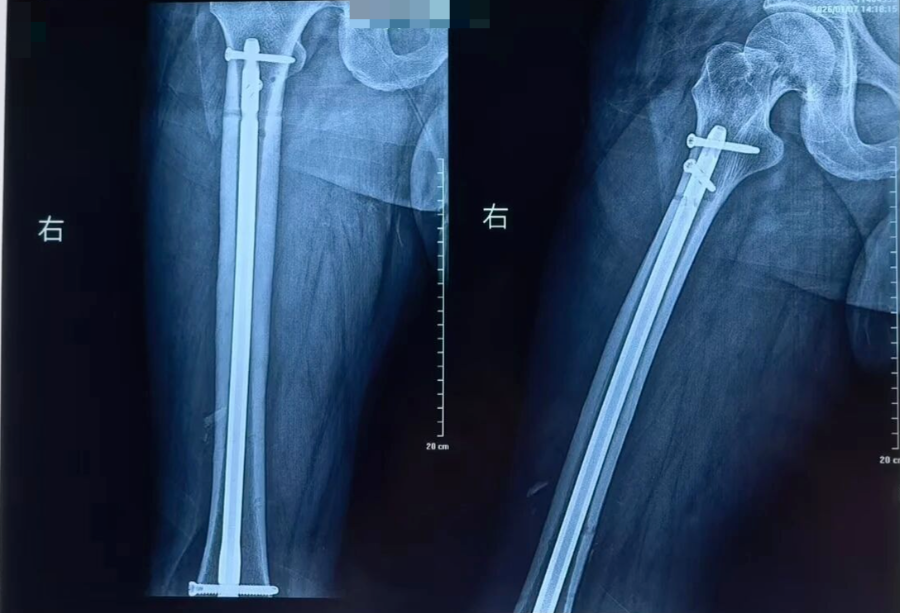

抢救团队凭借丰富的创伤救治经验,在黄金时间内完成伤情评估与抗休克治疗。随后为患者施行骨折复位外固定、髓内钉内固定、解剖钢板内固定等关键手术治疗。手术过程顺利,患者出血得到有效控制,骨折部位获得稳定固定,术后生命体征平稳,安全转入ICU接受进一步监护与支持治疗。